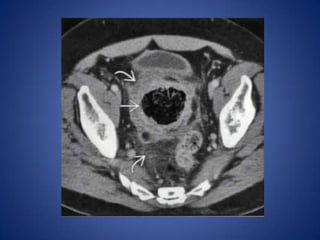

Diverticulitis

• Most common cause in middle-aged and

elderly

– Can affect patients as young as 25

• Usually long ( 10- 1 5 cm) segment of wall

thickening, luminal narrowing, pericolonic

infiltration

• Extraluminal collections of gas or fluid help

confirm diagnosis

Diverticulitis • Most commoncause in middle-aged and elderly – Can affect patients as young as 25 • Usually long ( 10- 1 5 cm) segment of wall thickening, luminal narrowing, pericolonic infiltration • Extraluminal collections of gas or fluid help confirm diagnosis